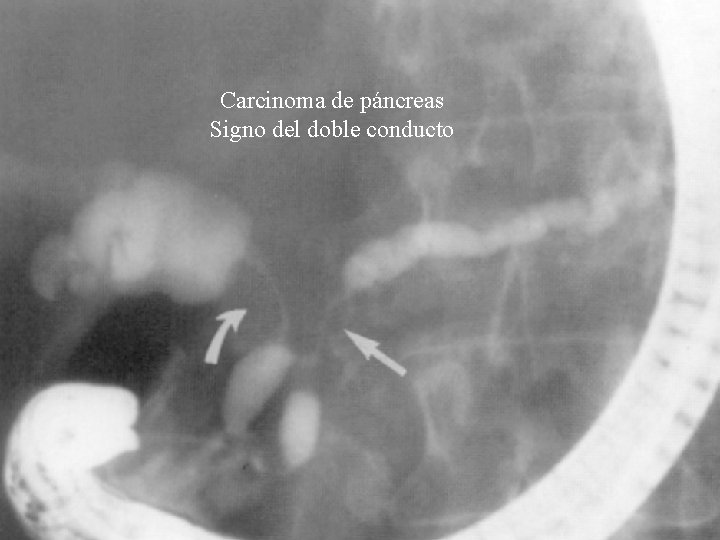

Tumores Pancreáticos n Hallazgos de la pancreatografía – Obstrucción: stop abrupto, excéntrico, irregular – Estenosis: larga, única, irregular, excéntrica con desaparición conductos secundarios – Afilamiento ductal – Cavidad (necrosis tumoral) – Simulación pancreatitis crónica -8%– Normal -8%- n Hallazgos de la colangiografía – Estenosis biliar » En tumores cabeza páncreas (60 -75%) » Signo del doble conducto

Carcinoma de páncreas Signo del doble conducto